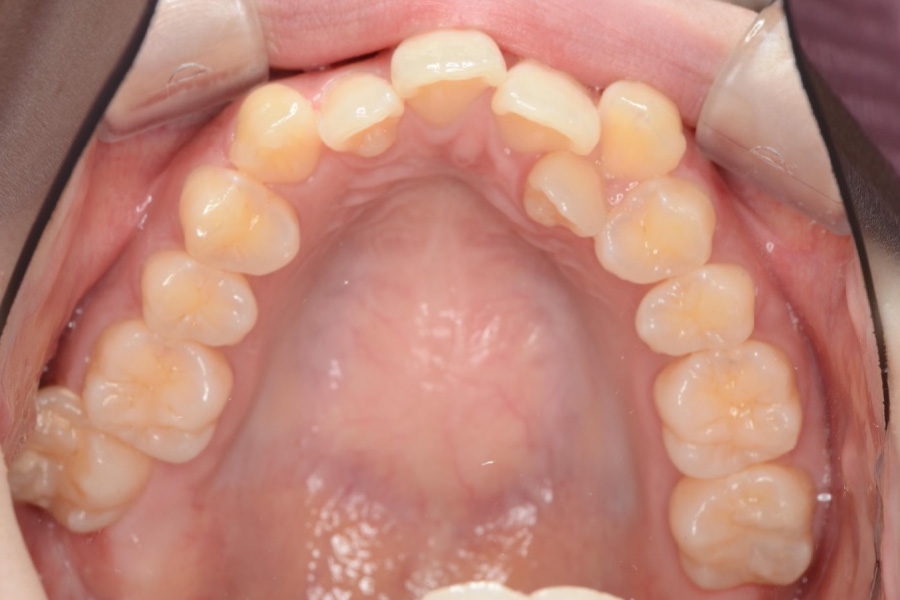

【20代女性】

全体のガタつきを

インビザライン矯正で治療したケース

治療前

主訴 全体のガタつきが気になる

治療内容 インビザライン矯正

小臼歯抜歯